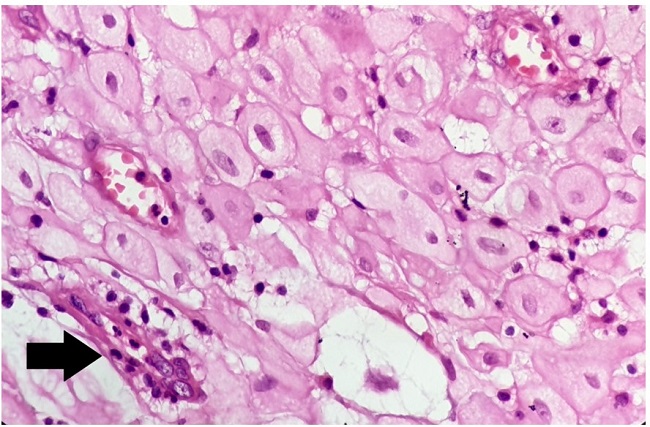

These decidual cells were polygonal, with large nuclei, abundant homogenous eosinophilic cytoplasm (Figure 2), and associated with vacuolar degeneration in some places.

Microscopically, decidual cells are commonly found to be associated with endometrial tissue present over a scar. The lesions may frequently present as small cell groups or single-cell clusters, and uncommonly, they are in the form of widespread-diffuse deciduosis that completely occupies the scar along with the underlying adipose stroma. Our case presented with microscopic features depicting the latter. Decidual cells are generally large and polygonal, with homogeneous, eosinophilic cytoplasm associated with varying degrees of vacuolar degeneration. Decidual cell vacuolization is related to the duration of the pregnancy. Stroma may also show myxoid deposit due to vacuole rupture if the decidual cell cytoplasmic vacuolar degeneration is over 50%.5 Our case did present some degree of vacuolar degeneration; however, myxoid changes were not noted.